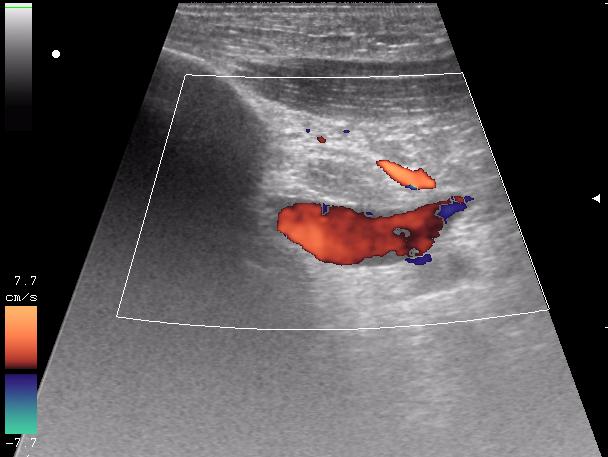

и в отношении второго снимка: там какой именно сосудистый пучок? - и что именно исключали этим сканом

исключали повреждение отломками подключичную артерию и вену ( был огроменный отек)

кстати, вот вена